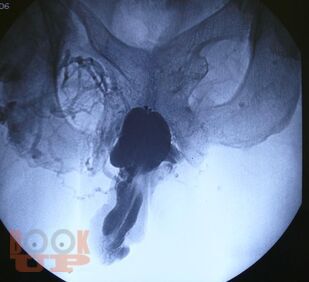

Динамическая кавернозография в диагностике патологии кавернозного бассейна полового члена

В учебном пособии представлены вопросы метода рентгеновского исследования заболеваний кавернозного бассейна полового члена, некоторые анатомо-физиологические аспекты эрекции, показания и противопоказания к проведению динамической кавернозографии, описана методика проведения динамической кавернозографии, а также представлен разработанный авторами алгоритм обследования пациентов с эректильной дисфункцией. Учебное пособие предназначено для врачей рентгенологов и урологов.